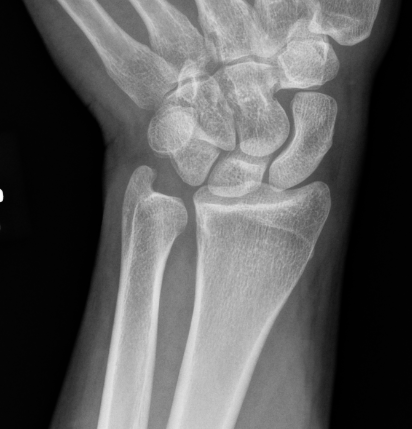

Isolated dorsal dislocation DRUJ

Isolated dorsal DRUJ instability with ulna sided TFCC tear

Xray

True lateral

- radial styloid overlies proximal scaphoid / lunate / triquetram

Dorsal subluxation of the distal ulna